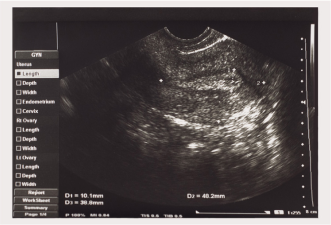

УЗИ на 19 неделе беременности

Прошла практически половина беременности. Вам может быть назначено УЗИ на 19 неделе беременности, или его назначат на ближайшие недели. В ходе процедуры врач определит примерный вес и рост вашего ребенка, тщательно осмотрит все части тела крохи, его внутренние органы, включая сердечко, чтобы исключить какие-либо аномалии. Это так называемый второй УЗИ-скрининг. Он может назначаться одновременно с лабораторными тестами.

Во время приема во втором триместре вам также предстоит пройти несколько анализов. Анализы мочи, сахара в крови, медицинский осмотр и другие лабораторные тесты обычно выполняются во время планового осмотра5.